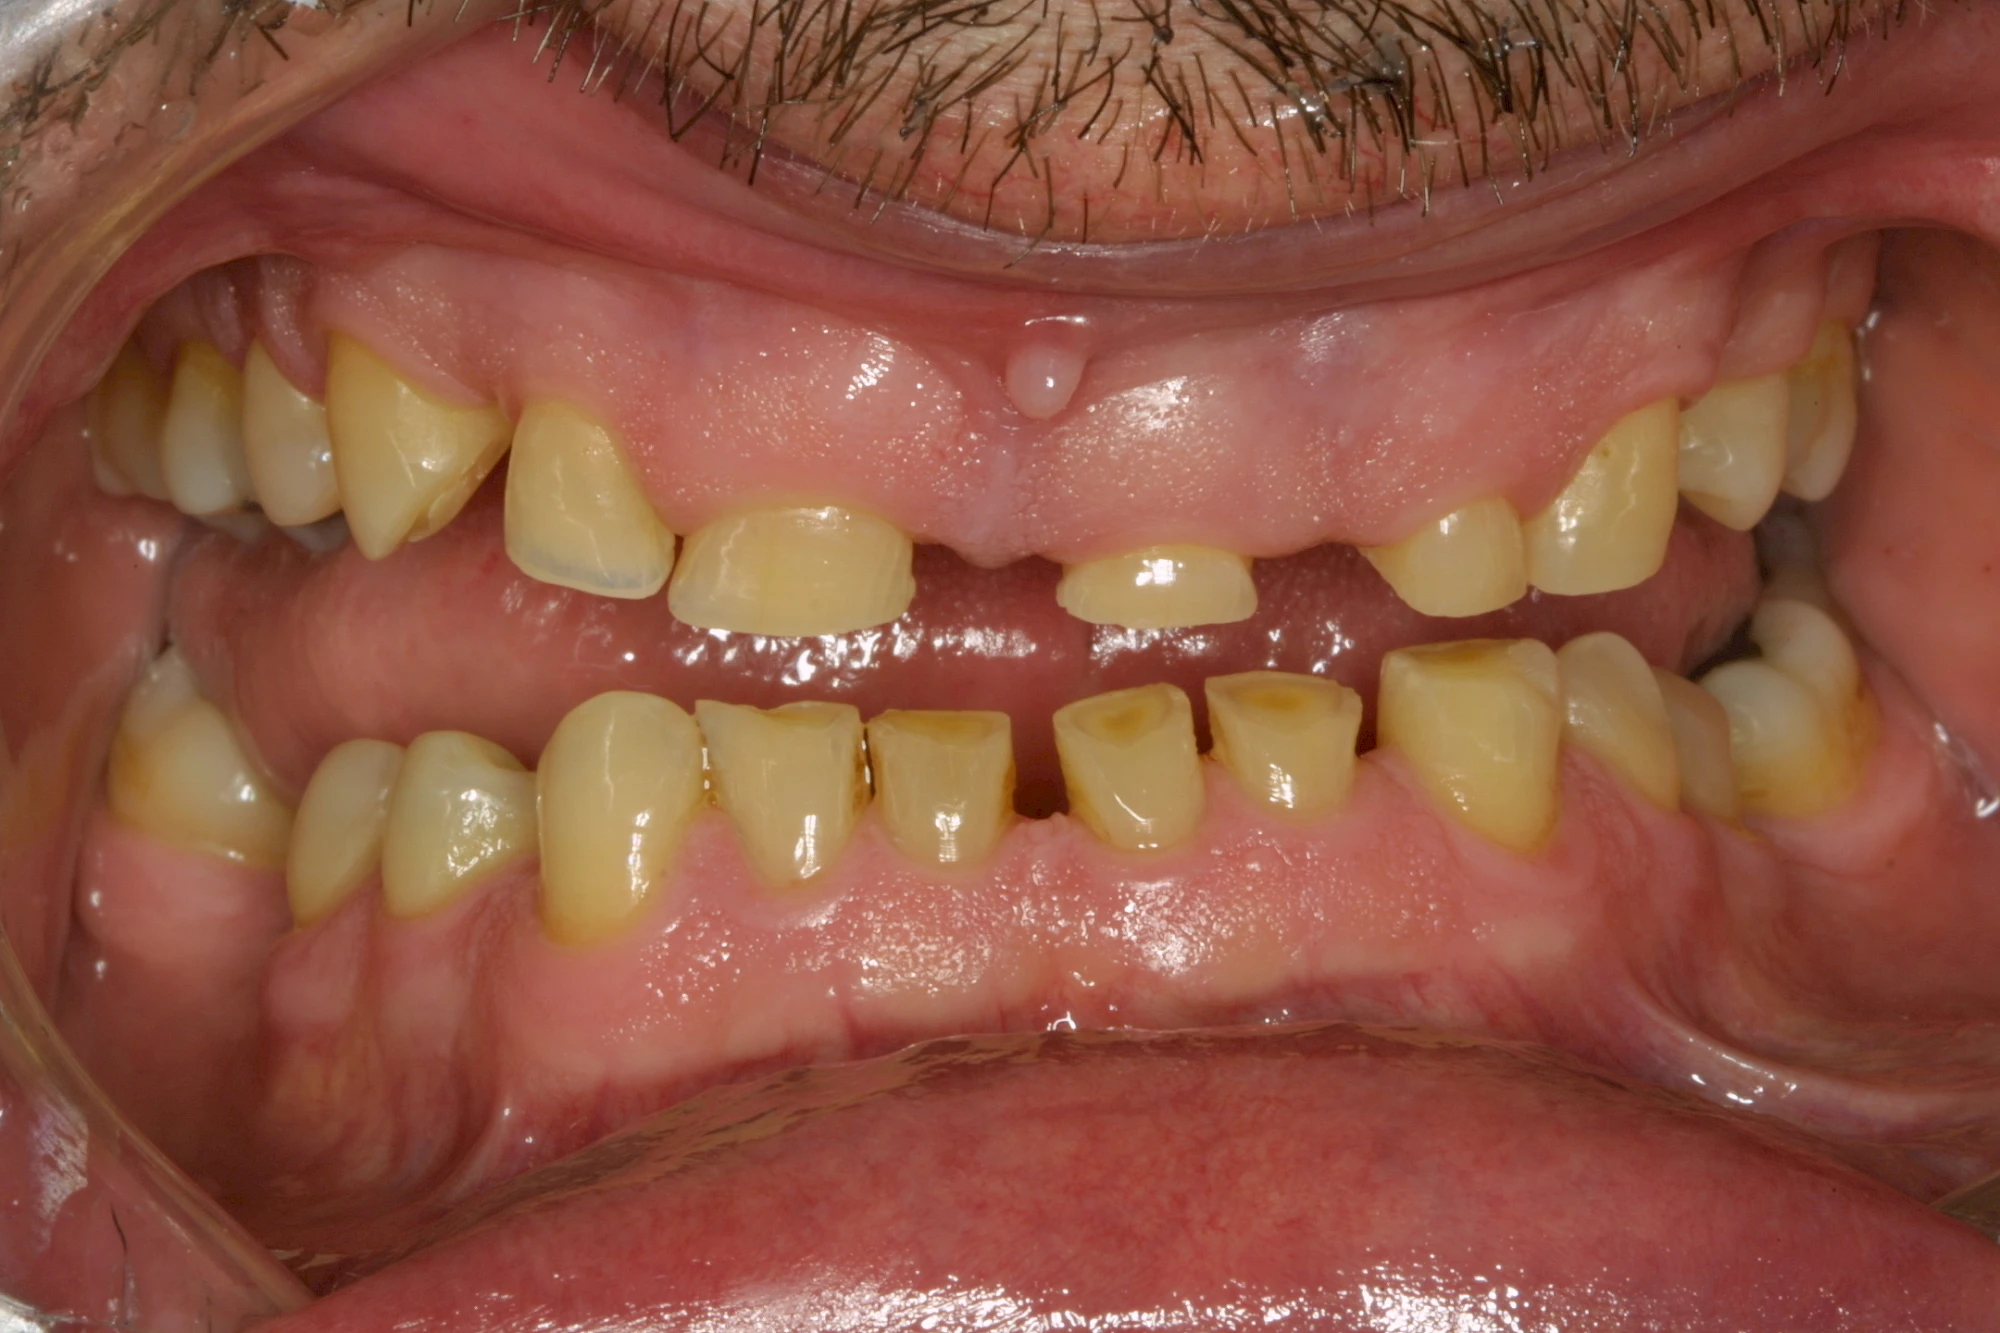

Über die Zeit können verschiedene Prozesse die Zahnhartsubstanzen aufzehren:

- Abnutzung durch Kauen (Abrasion) oder duch durch übermäßiges Knirschen bzw. Pressen (Attrition)

- Säurebedingte Auswaschung (Erosion)

- Knirschen bzw. Pressen und ungünstige Putztechnik (Druck): keilförmige Defekte